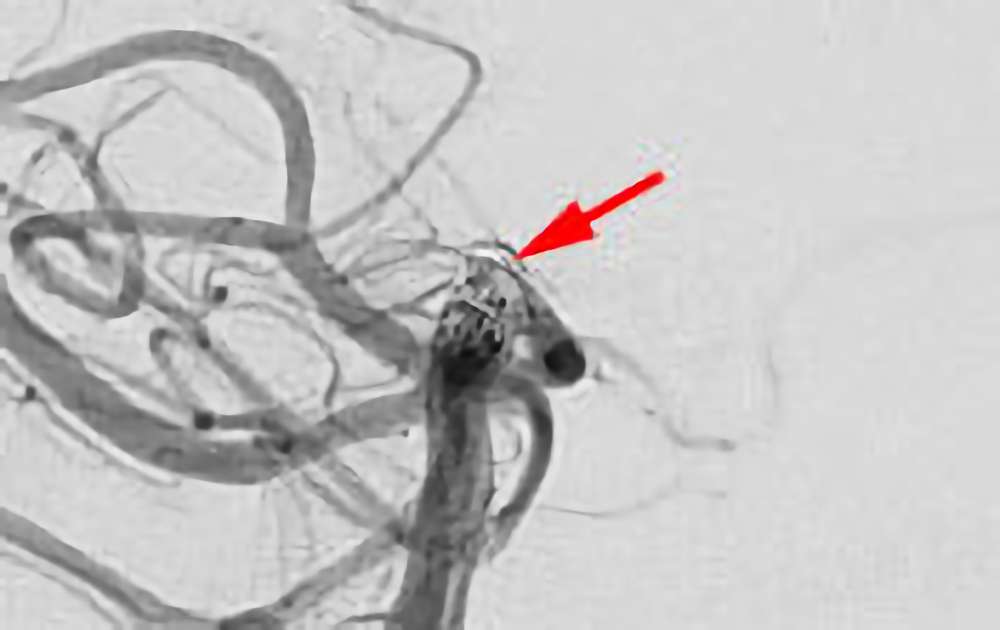

'26年4月

左内頚動脈脳動脈瘤

70代

大阪府の病院

No.1630 手術前

No.1630 手術中

No.1630 手術後